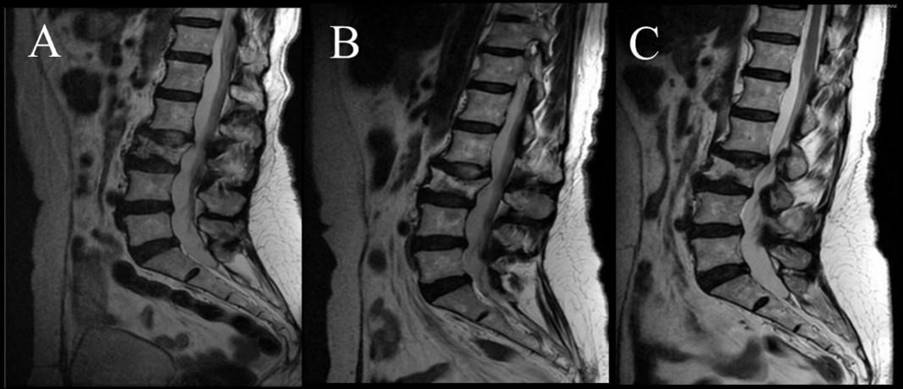

En diciembre de 2020, la paciente inició un tratamiento a base de ClO2 oral, agregando 1 ml del vehículo dimetilsulfóxido (DMSO) al 70 %. En 2021, la paciente presentó dolores lumbares intensos debido a una fractura de L3 en terreno patológico, rechazó la cirugía y recurrió al uso de ortesis lumbar durante 3 meses. Con el objetivo de aumentar la bio-disponibilidad de ClO2, se complementó la vía de administración oral con enemas de absorción. Además, la paciente practicó ayuno intermitente durante 18-20 horas y consumió suplementos diarios por la noche de 5 000 UI de vitamina D3, 1 g de vitamina C, 1,1 g de potasio y 250 mg de magnesio. La paciente continúa un seguimiento de 4 años desde el diagnóstico, en los que se observó una importante recuperación ósea en la fractura vertebral (figura 1), sin reacciones adversas. La paciente se encuentra en remisión completa.

Figura 1. Imágenes de RM en vista sagital muestran aumento visual en la densidad ósea en la L3 de paciente con linfoma no Hodgkin metastásico. Fractura patológica en la vértebra L3, 2020 (A), y la recuperación de la misma en 2021 (B) y 2022 (C).